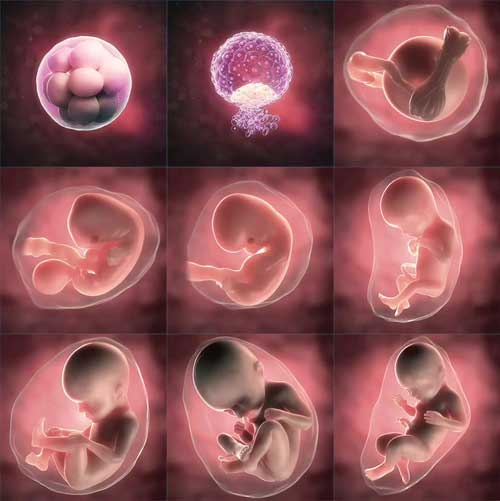

مراحل رشد جنین هفته به هفته با عکس در رحم مادر

رشد جنین در رحم مادر سفری شگفت انگیز و پیچیده است که با تغییرات قابل توجهی در هر هفته همراه است. آگاهی از این مراحل نه تنها به مادران باردار کمک می کند تا بارداری خود را بهتر مدیریت کنند بلکه به درک عمیق تر از زندگی جدیدی که در حال شکل گیری است می انجامد. به همین دلیل در این بخش به بررسی روند رشد جنین طبق جدول ماه های بارداری می پردازیم.

در این مرحله پس از لقاح سلول تخم به سرعت تقسیم می شود و به دیواره رحم می چسبد. پیش روی های اولیه شامل تشکیل بلاستوسیست و آغاز تکامل جنین است.

در هفته چهارم قلب کوچک جنین شروع به تپیدن می کند. اندام های ابتدایی مانند مغز ستون فقرات و چشم ها شروع به شکل گیری می کنند.

در این دوره دست ها و پاها ظاهر می شوند و مغز به طور قابل توجهی رشد می کند. جنین تقریباً به اندازه یک گیلاس است.

در این مرحله ارگان های اصلی بدن جنین تکامل می یابند و او می تواند حرکات خود را آغاز کند هرچند مادر هنوز آن را حس نمی کند.

این دوره با رشد سریع استخوان ها عضلات و سیستم عصبی همراه است. جنین اکنون می تواند حرکات خود را بهتر هماهنگ کند.

هفته بیست و یکم تا بیست و چهارم : رشد حسی

هفته بیست و پنجم تا سی ام : آمادگی برای تولد

هفته سی ویکم تا سی وپنجم : تکمیل اندام ها

هفته سی وششم تا چهلم : انتظار تولد

مراحل رشد جنین از هفته اول تا چهل تجربه ای منحصر به فرد است که با مراقبت های مناسب می تواند سالم و ایمن طی شود. اگرچه هر بارداری متفاوت است اما مراجعه به پزشک و پیگیری منظم وضعیت جنین و مادر امری ضروری است.